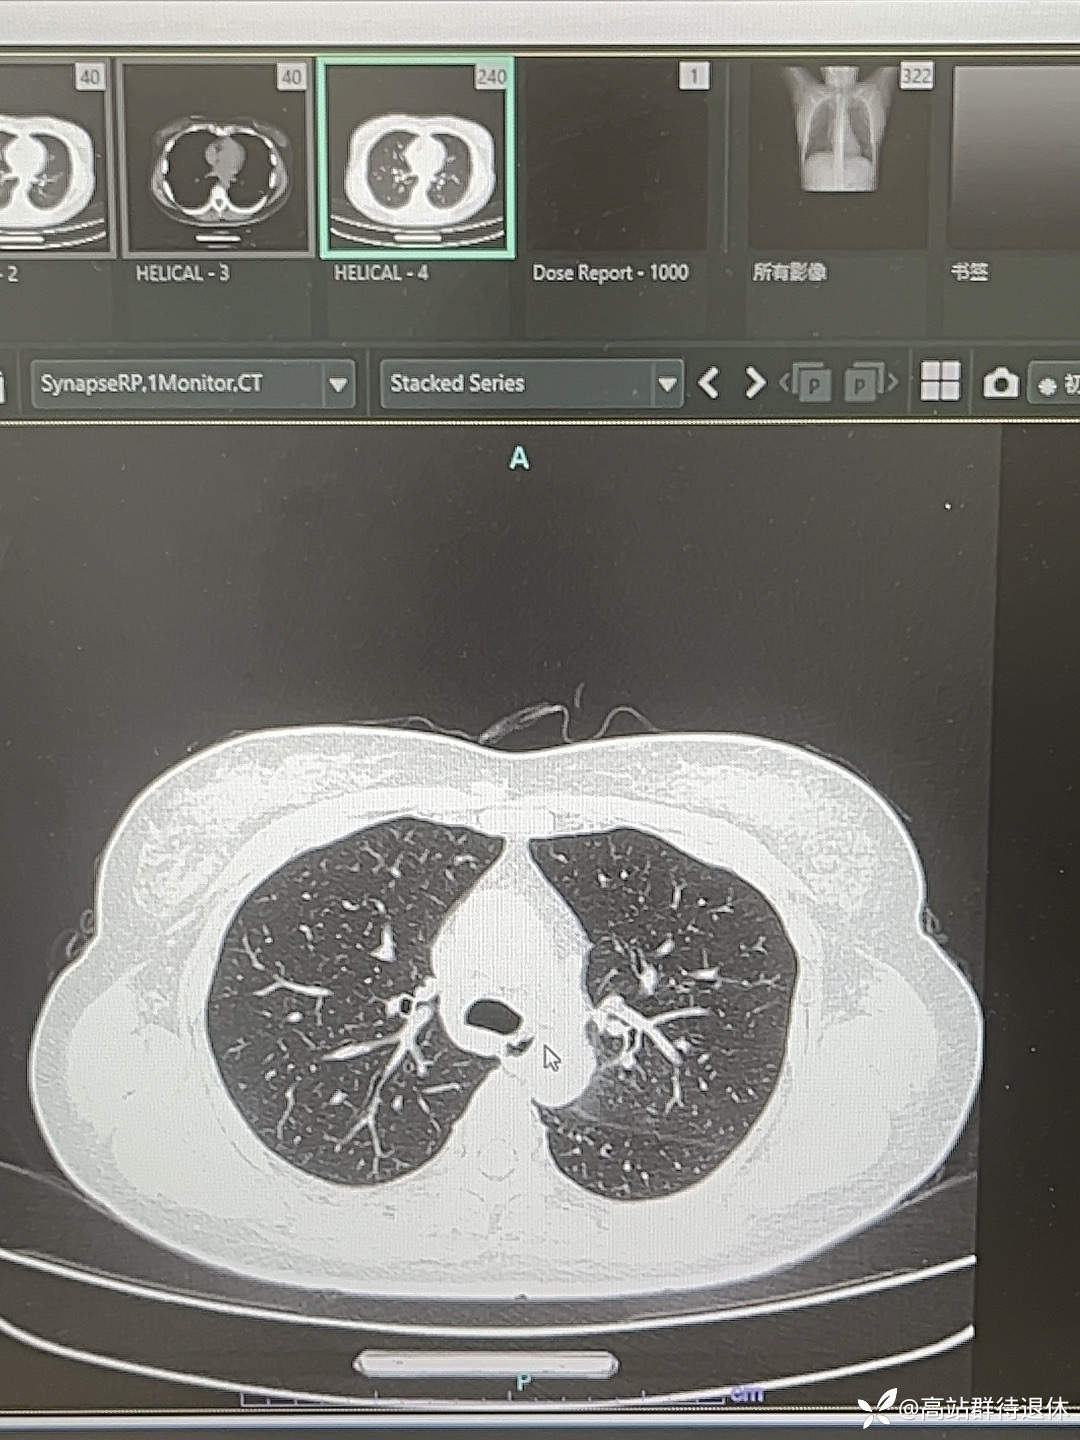

43岁,女性,既往健康,

【主诉】:咽痛20天

【现病史及既往史】:患者20天前无明显诱因出现咽痛,伴发热,咳嗽,咳痰,痰不易咳出,伴有头晕,恶心,无胸闷,心悸,在家口服肺宁颗粒,罗红霉素及阿奇霉素等药物(具体剂量不详),无缓解,故来我院救治,行相关检查后,以“发热待查”收入我科。患者自发病以来,饮食及睡眠欠佳,二便正常。既往阑尾炎及剖腹产手术,头孢过敏

8月17日血常规

8月18日血常规